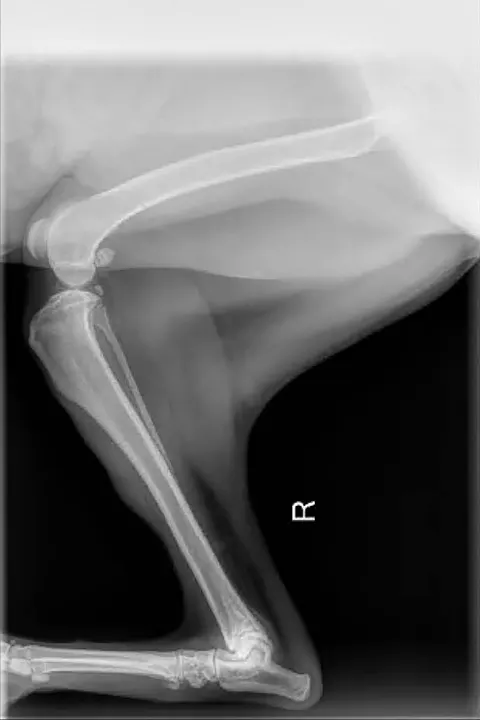

FIGURE 1

Lateral view in which increased flexion of the tarsus independent of the stifle can be seen. The stifle is extended to compensate for loss of functional limb length.